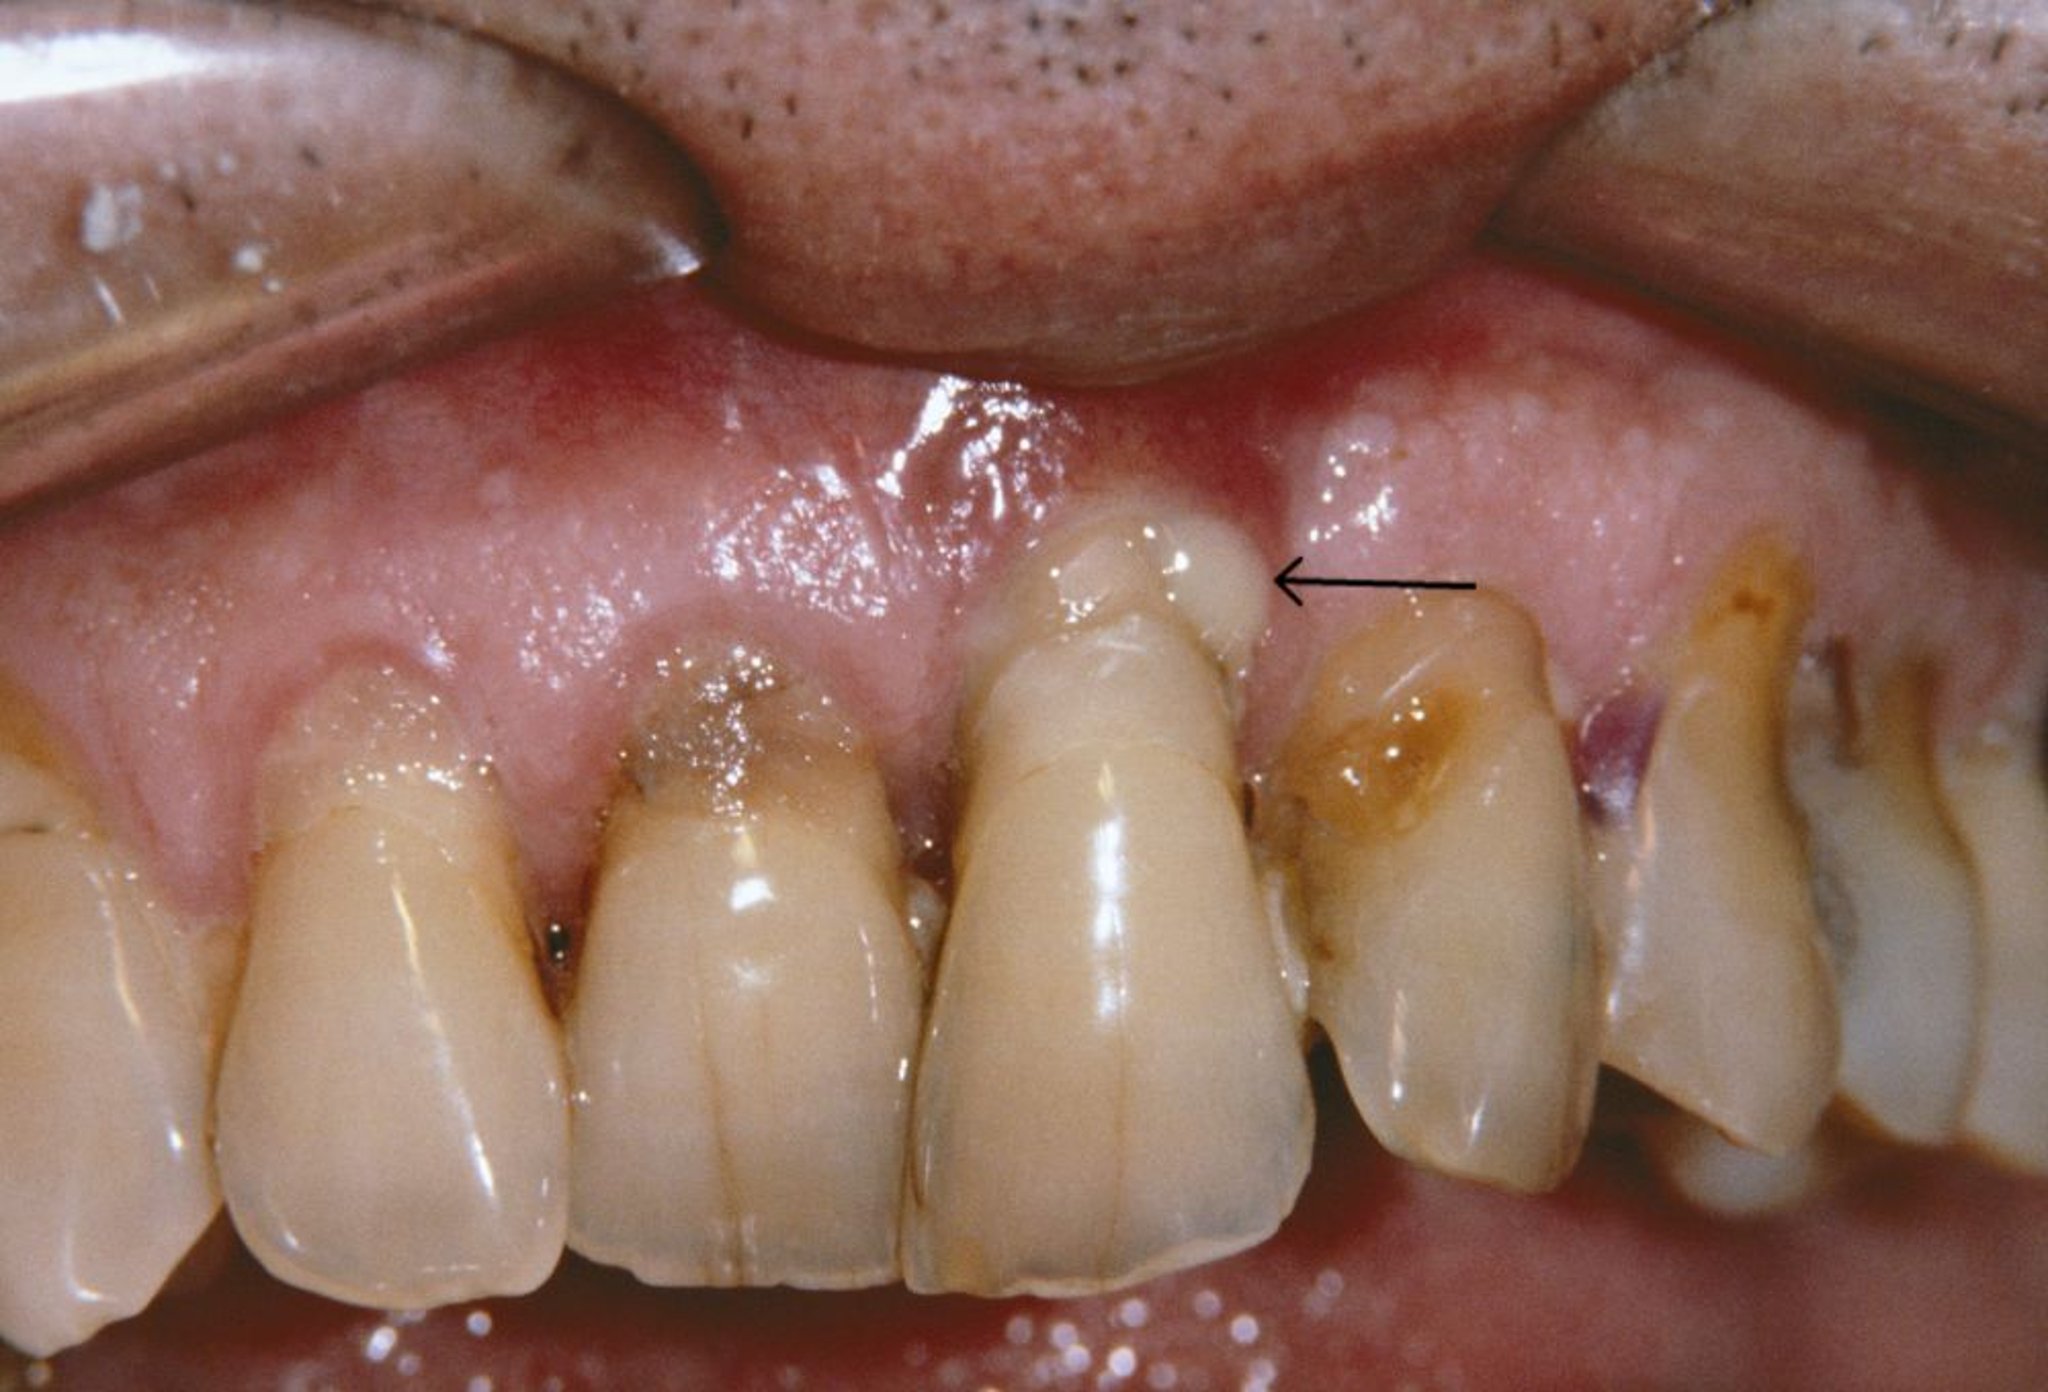

この写真には,歯周炎患者の退縮している歯肉および歯周膿瘍(矢印)が写っている。